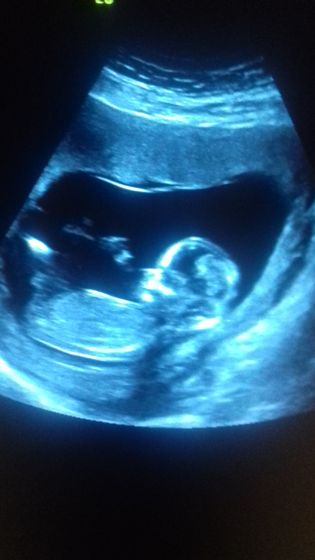

Балашихинский МОПЦ это, конечно, то еще заведение… Мне в поликлинике клялись, что очередей на скрининг давно нет (хотела просто платно пройти в Инвитро), поверила, пошла, просидела с 10.40 до 13.30 в очереди ? В коридорчике 15 кв м, куда поместилось еще 15 человек. Оставили синяк на руке, иголка, будто сапоги шить?В общем, больше не хочу туда ходить))) А так, подтвердили (пробубнили), что у нас все в срок и хорошо, и даже удалось фото с экрана сделать?

Ручкой машет, а вторая вроде за головкой! Поздравляю вас! Пол не предположили?

Спасибо) Да, так и есть про руки) А пол там не говорят. В инвитро предположили девочку, но это не точно на таком сроке)